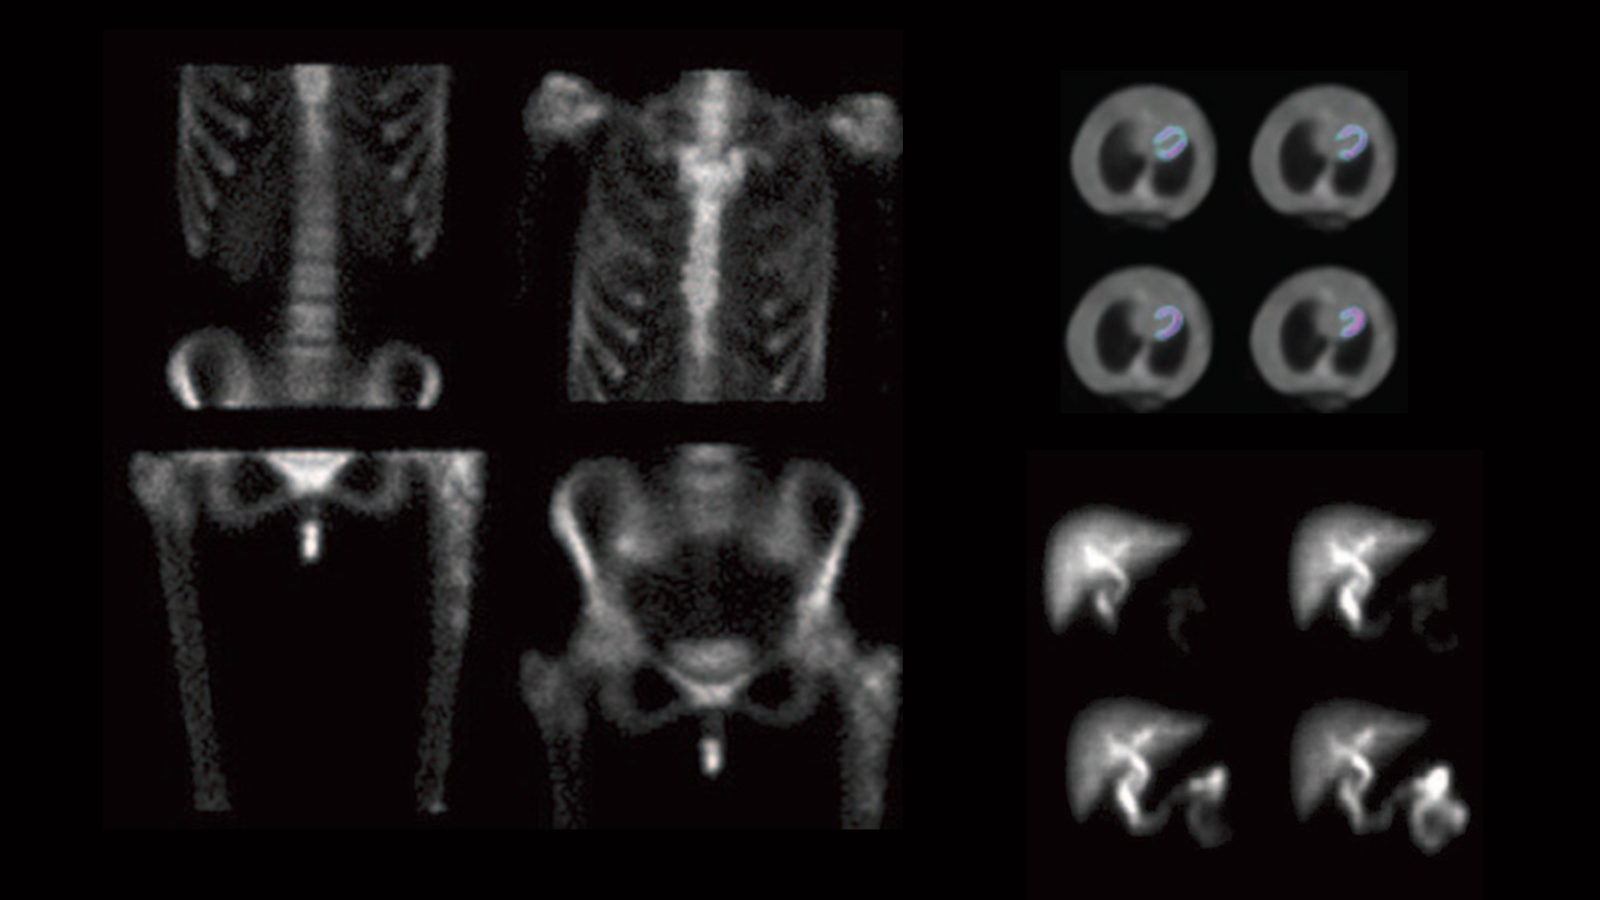

To use a gamma camera, physicians first inject into the bloodstream a small amount of a short-lived radioactive isotope, which sends out gamma rays as it decays. The patient must then lay very still inside a hospital’s tunnel-like gamma camera for five to 30 minutes as its detectors record the isotope’s emissions and create images that show doctors where the patient’s blood is flowing or blocked.

Today, Digirad provides onsite gamma imaging services in remote locations and produces two additional compact gamma cameras that have two or three of the thin, lightweight and adjustable detectors to produce clearer heart images in doctors’ offices or clinics.